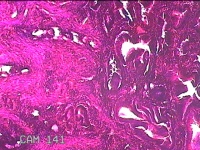

宫腔赘生物

性别

女

年龄

41岁

临床诊断

子宫异常出血 子宫内膜息肉?高泌乳素血症待查 慢性宫颈炎

一般病史

阴道流血不规则22天。

标本名称

大体所见

灰白暗红色不规则肿物1.3x0.8x0.3cm两个,表面糜烂。